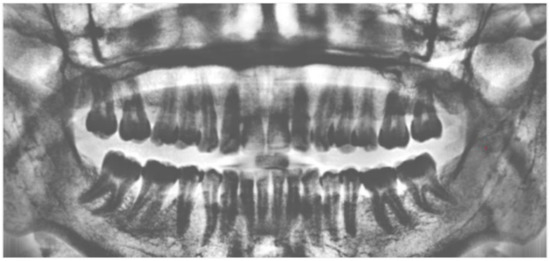

2.1.1. Sharpening

2.1.2. Image Contrast Adjustment

2.1.4. Adaptive Histogram Equalization

2.2. Image Segmentation

3. Results